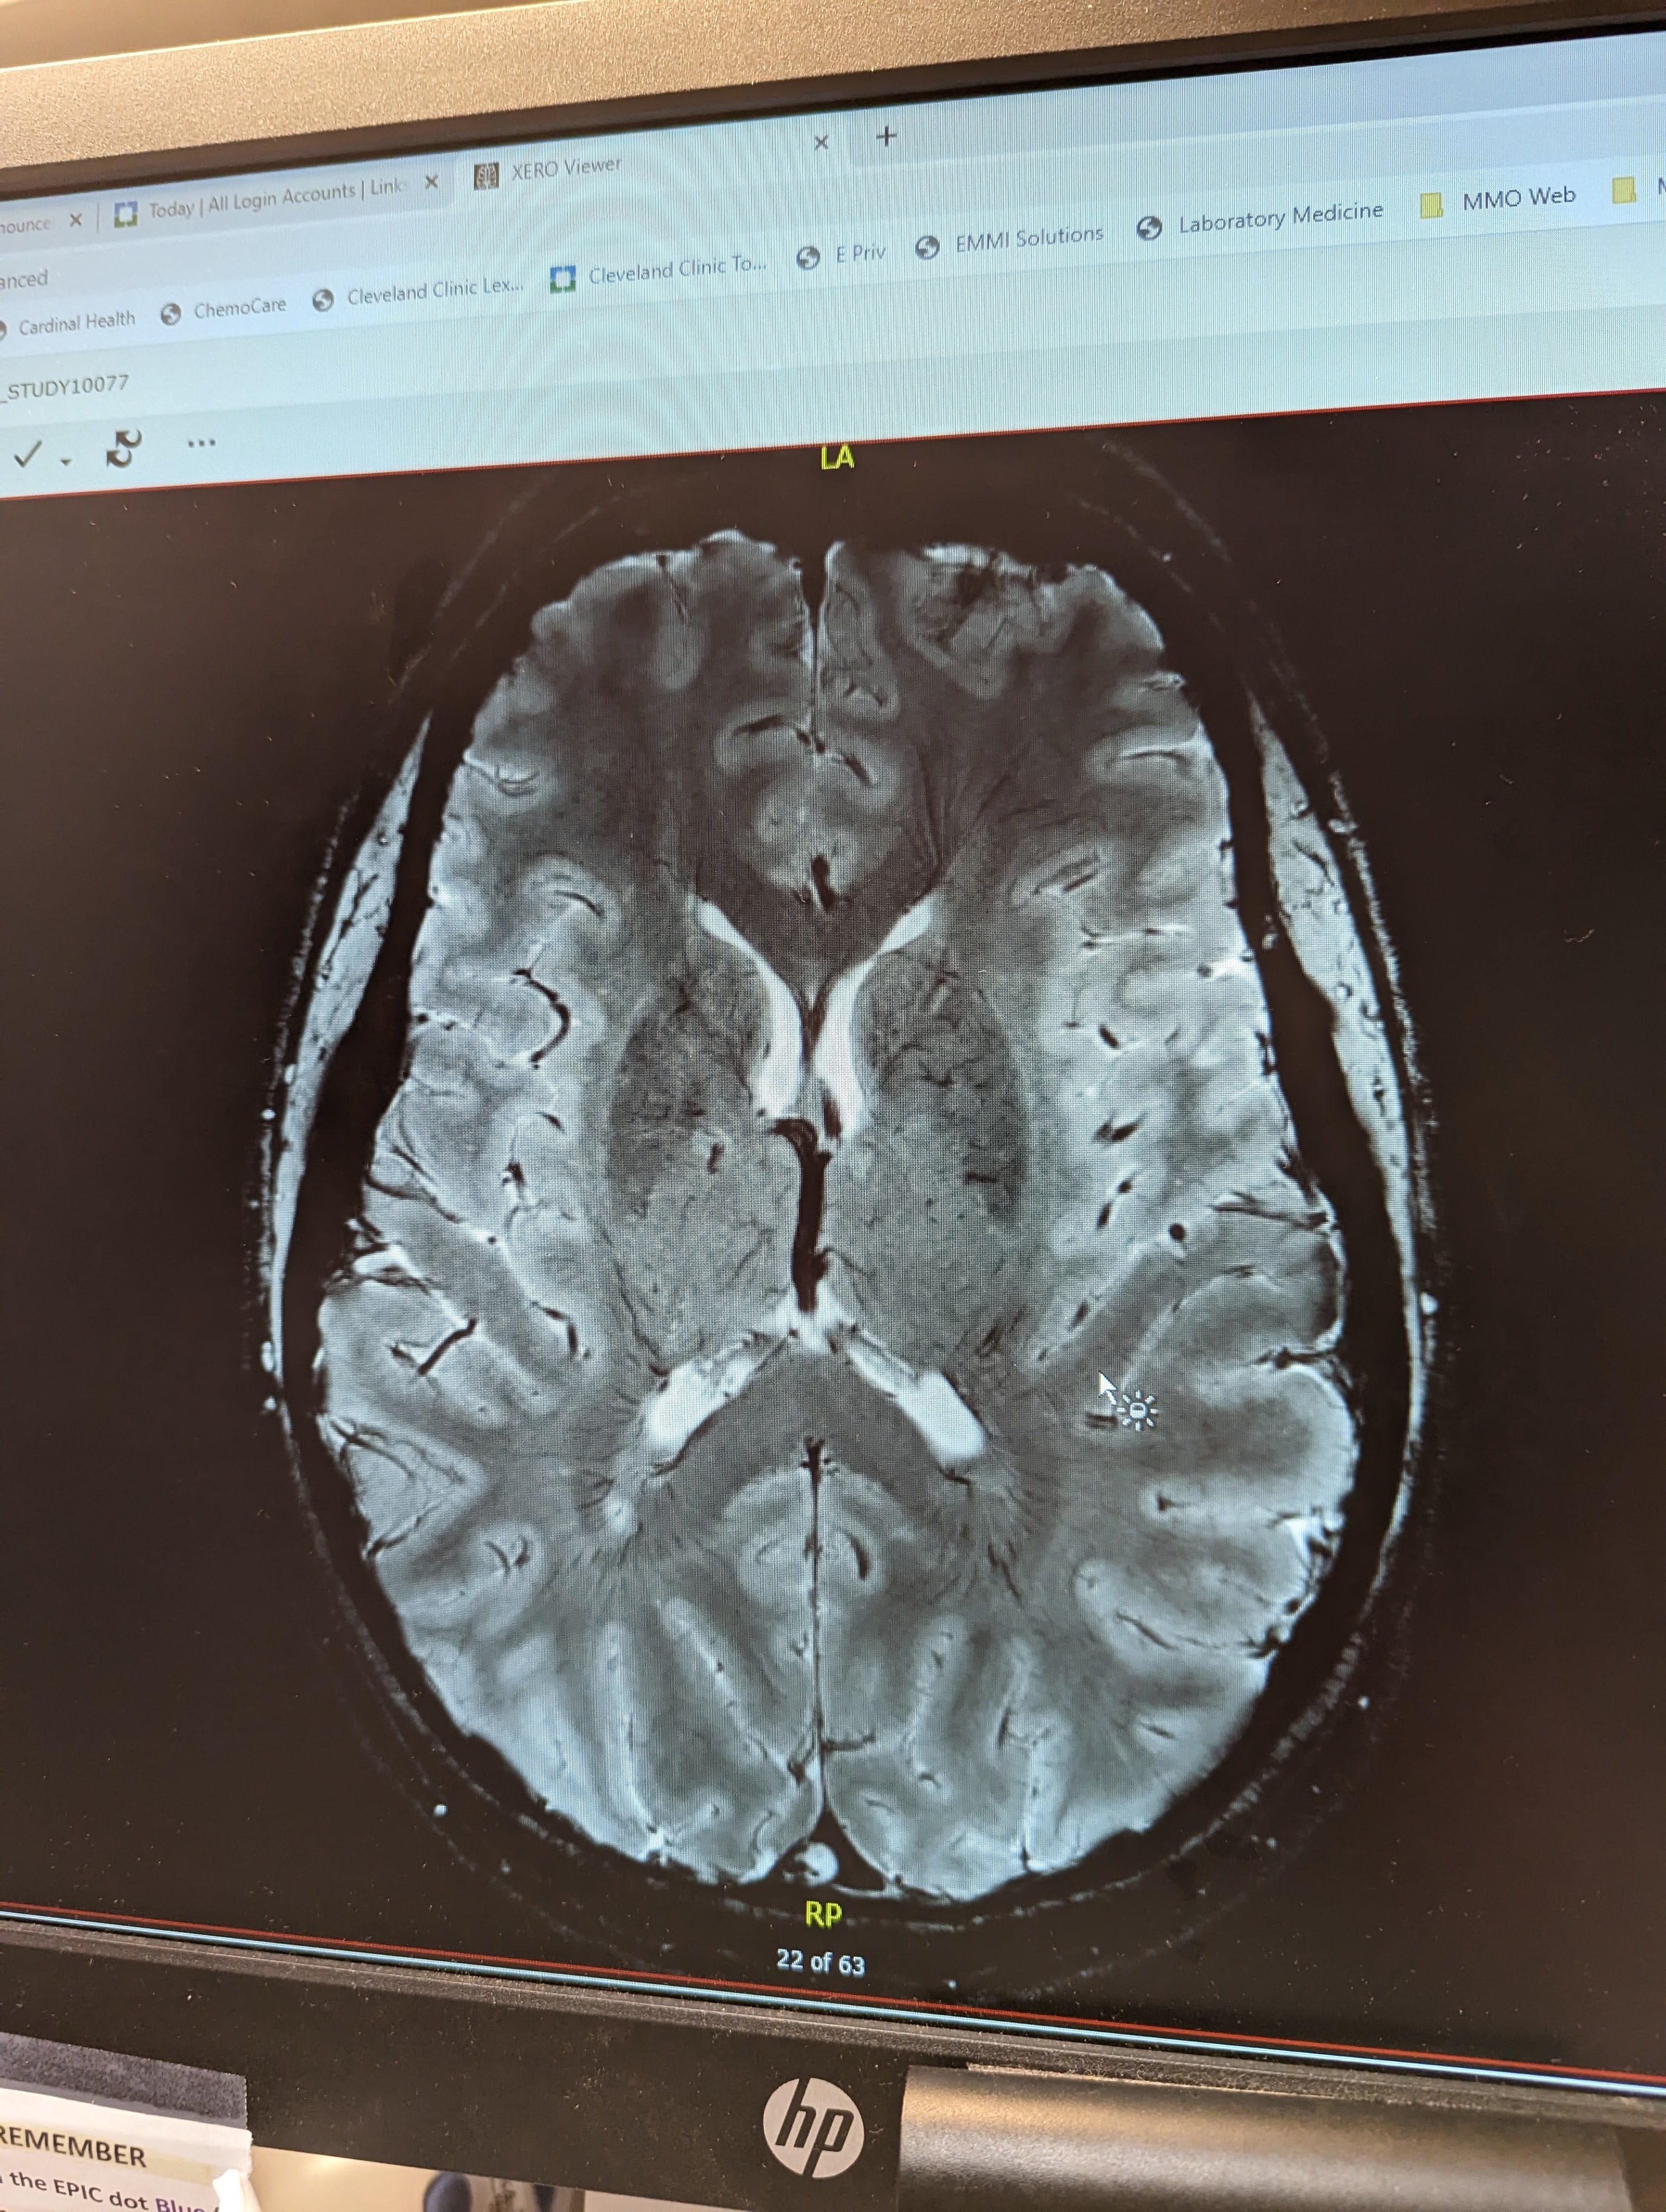

I’ve spent the last two years being poked, prodded, and touched. I’ve been told to push down, pull up, push back, force, try, think, do… over and over again as if the request might alter the final result despite my broken nerve connections and neurodegeneration. I’ve had strangers’ fingers touch the sides of my body — face, arms, legs, shins, and feet to test if sensation is the same on each side. I’ve endured safety pin pricks and tuning fork vibrations. I’ve had my blood pressure and temperature checked three million times, on the hour. I’ve been given shots to prevent blood clots.

I did it all and I did it willingly. But looking back I can see the harm, the trauma, the changes caused. With each appointment I became more resigned to my fate. The tests inform the medical team but at a high cost. I had no right of refusal because I needed the information gleaned. But with each poke, prod, and touch of a stranger, my armor got thicker. Unbeknownst to me, my barriers were up and getting stronger each day. If I had to be touched by medical personnel, then I exhibited some control over the people in my life by saying no to hugs and comfort. I overreacted by removing myself from the kind and healing touches.